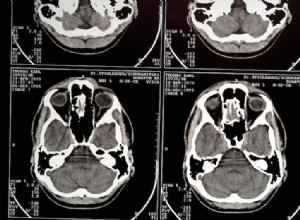

Nouveau traitement contre l'AVC : moins de séquelles et de lésions cérébrales